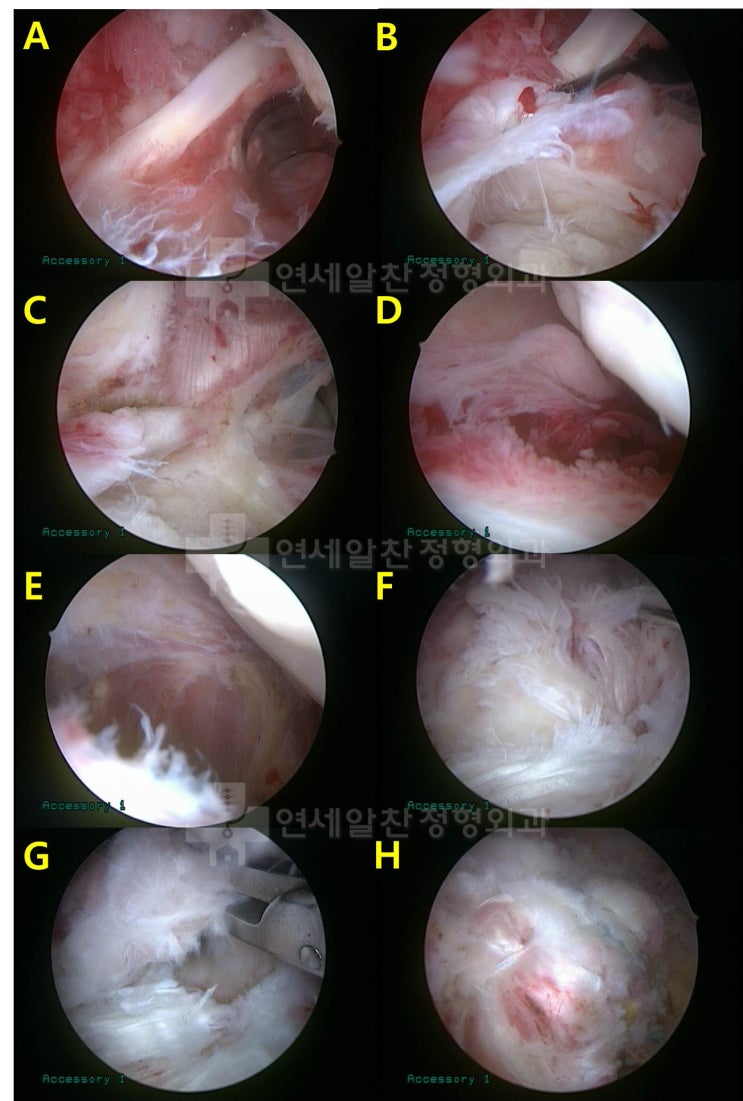

회전근개파열 에서 이열교량형 봉합법 에 대한 고찰

회전근개 파열 을 수술할 경우 봉합법에 대한 문의를 하는 경우가 종종 있다. 회전근개파열 이 있는 경우 ...